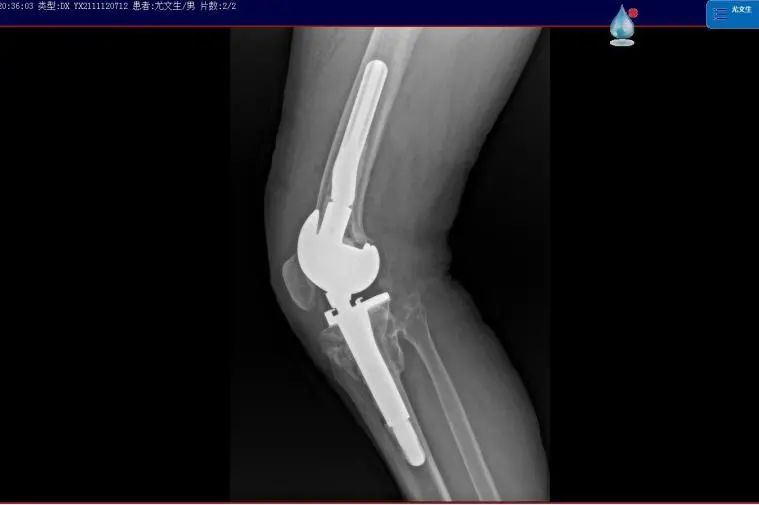

58岁的尤大叔是晋江内坑人,9年前因外伤导致右侧胫骨近端骨折,在外院进行手术治疗。但术后恢复欠佳,尤大叔行走状况逐渐受限,右膝关节严重外翻,因经济原因一直未进行系统治疗,生活、工作上带来的不便让他苦不堪言。

▲严重外翻畸形

▲术前影像